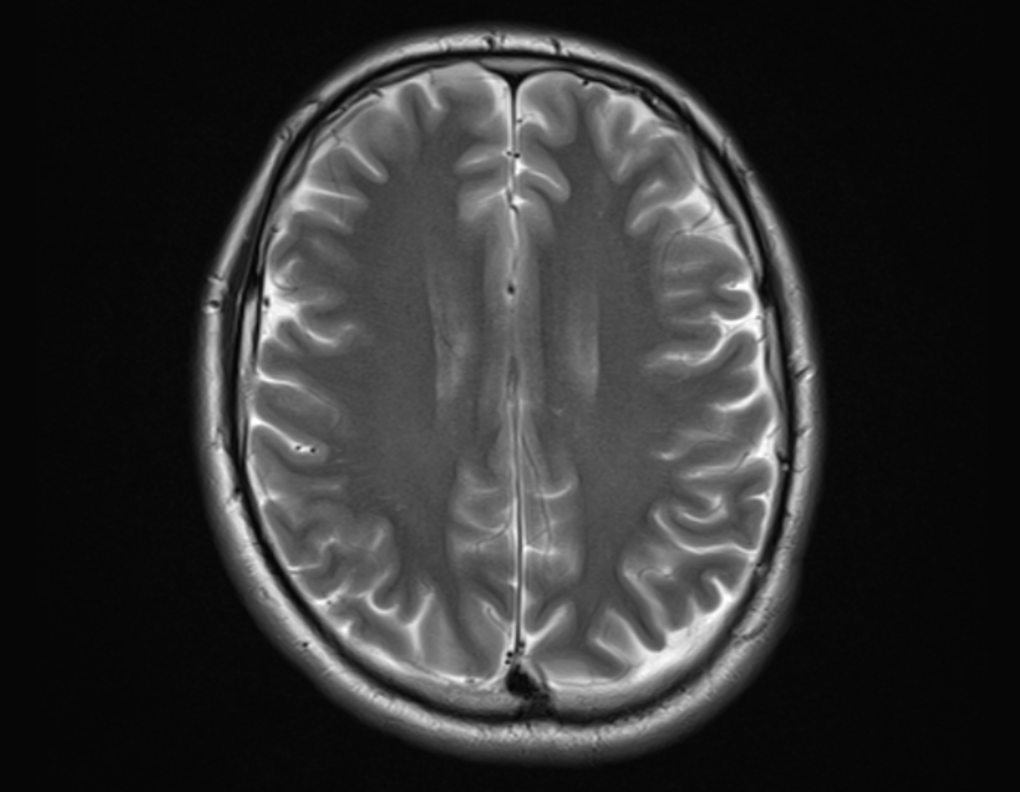

Most DICOM applications today read common imaging modalities like CT, MRI, and ultrasound images. Features such as multiplanar reconstruction (MPR), particularly 3D reconstruction, are needed for treatment planning. Volume rendering, maximum and minimum intensity projections (MIPs) aid in diagnosis as well as in research. Image fusion, such as PET to CTs or PET to MRIs can also help in diagnosis and reporting.

MANGO is an advanced DICOM application which requires some technical coding before it can be used. It has several advanced features, including conversion, anonymization and editing images. Other versions of Mango (Papaya and iMango) can be accessed from the browser directly or an Apple iPad. The application is under constant development, possible due to grants from the National Institute of Mental Health and the National Institute of Biomedical Imaging and Engineering. Therefore, it keeps improving in its functionality. Advanced options like behavioral analysis, disease analysis, and brain separation modalities make it particularly useful for neuromedicine. It does not offer cloud storage.